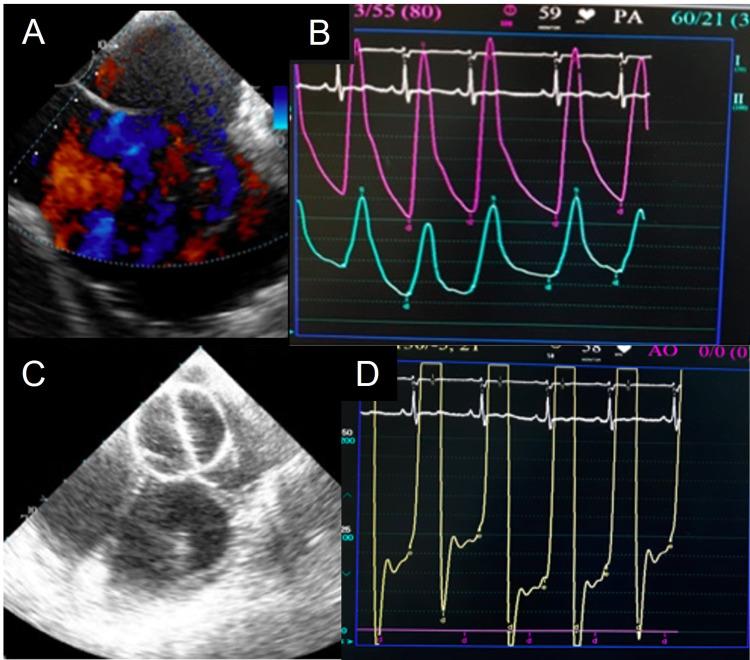

目的 由于心房左向右分流的长期影响,老年人群经导管房间隔缺损(ASD)封堵术面临更大挑战。本研究分析了50岁及以上老年患者经导管ASD封堵术中遇到的挑战。方法 分析2015年6月至2021年4月期间接受经导管ASD封堵术的40岁及以上患有显著继发孔型ASD的成人。根据对治疗方案改变的影响,将挑战分为主要挑战和次要挑战。患者按年龄分为三个亚组。第1组由40 - 49岁的患者组成(n = 13),第2组由50 - 59岁的患者组成(n = 16),第3组由60岁及以上的患者组成(n = 8)。结果 共分析了37例患者。遇到的挑战包括心律失常、肺动脉高压、左心室舒张功能障碍、出血、中风、冠状动脉疾病(CAD)、高血压和气道疾病。13%的挑战出现在术前,而79%的挑战出现在术中,8%的挑战出现在术后。35例患者(94.6%)接受了经导管ASD封堵术。2例患者(5.4%)分别因严重舒张功能障碍和相关CAD未接受经导管ASD封堵术。10例患者遇到11项主要挑战,其中1例患者同时面临出血和心律失常双重挑战。13例患者(35.1%)手术顺利,未遇到任何挑战。20例患者遇到27项次要挑战,部分患者同时存在多项主要和次要挑战。患者在平均28个月的随访中情况良好。结论 40岁及以上老年患者经导管ASD封堵术安全有效。此类高危患者容易面临各种挑战,如果在正确理解生理改变并预期手术各阶段偏离过程的基础上进行最佳监测,这些挑战是可以有效管理的。